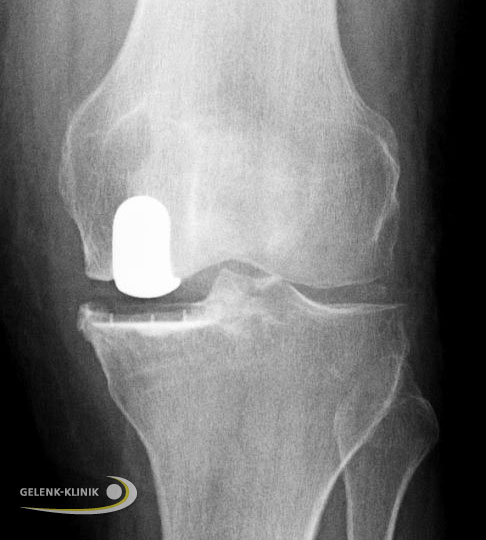

Vor allem Knieprothesen betroffen

Knieprothesen bestehen häufig aus Chrom-Molybdän-Legierungen, die Kobalt, Chrom und oft auch Nickel enthalten. Diese Metalle gelten als klassische Kontaktallergene, weshalb bei entsprechend sensibilisierten Personen Implantatallergien auftreten können. Die weniger allergisierenden, bei Hüftprothesen üblichen Titanimplantate sind für den Einsatz in Prothesen am Kniegelenk zu weich. Deshalb werden am Kniegelenk die härteren Prothesen aus einer nickelhaltigen Stahl-Legierung eingesetzt.

Bei sicher nachgewiesener Kontaktallergie verzichten wir heute auf die Verwendung von Chrom-Kobalt-Legierungen als Prothesenimplantatmaterial. Die Zusammenhänge zwischen allergischer Hautreaktion und der Reaktion im umgebenden Gewebe des Implantats können zwar nicht sicher vorhergesagt werden. Bei nachgewiesener Allergie gegen Inhaltsstoffe einer Kobalt-Chrom-Molybdän-Legierung können wir durch Allergieimplantate aber das Komplikationsrisiko minimieren.

In Abhängigkeit vom versorgten Gelenk können die Operateure spezielle Gleitpaarungen wie Polyethylen, Keramik oder alternative Materialien verwenden.

Alternativmaterialien sind keramikbeschichtete oder titanbeschichtete Metalle und vollkeramische Prothesen, soweit sie am vorgesehenen Einsatzort möglich und ausreichend sicher sind. Dabei geht es vor allem um Knieprothesen mit ihren allergenen Bestandteilen Nickel, Chrom und Kobalt. Diese Implantate können mit einer oder mehreren Schichten aus einer Titan- oder Keramikbeschichtung versiegelt werden. Man spricht in diesem Zusammenhang von "Allergieimplantaten". Zur Haltbarkeit dieser Allergieimplantate gibt es noch keine nachteiligen Erfahrungen. Wegen der deutlich höheren Kosten für die beschichtete Endoprothese werden für die titanbeschichteten Modelle die Zusatzkosten nur bei Patienten mit nachgewiesener Allergie vom Versicherer übernommen.